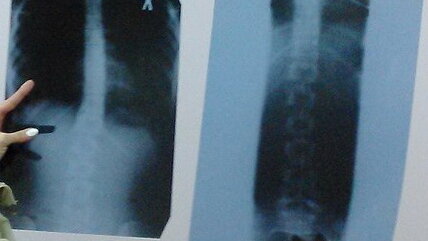

Как привести позвоночник в порядок

Знаете ли вы, что у космонавтов в невесомости рост может увеличиваться на 3 %? У этого феномена есть объяснение: так как в невесомости позвоночник теряет свои изгибы, мышцы расслабляются, зазоры между позвонками увеличиваются, сам позвоночный столб вытягивается, а вместе с ним и рост человека. По возвращении на Землю сила притяжения начинает действовать, и все возвращается в привычное состояние. Для среднего роста (около 170 см) 3 % — это приблизительно 5 см. Хотели бы вы так увеличиться в росте? Этого можно добиться, не покидая нашу Землю...

Учимся исправлять мышечные дисбалансы в областях грудного и поясничного отделов позвоночника — так можно даже прибавить в росте! Кривой позвоночник, понятно, короче прямого — и ты вместе с ним. Горбишься? Выполняй 3–5 раз в неделю этот комплекс упражнений, чтобы подрасти (в отдельных случаях прогресс достигает 3-5 см). Ты не просто станешь красавцем, но и избавишь себя в будущем от болезней, которые вызывает неправильная осанка. 1. Пугало Зачем Чтобы укрепить мышцы, вращающие плечо наружу. Их слабость способствует развитию избыточного кифоза грудного отдела позвоночника...